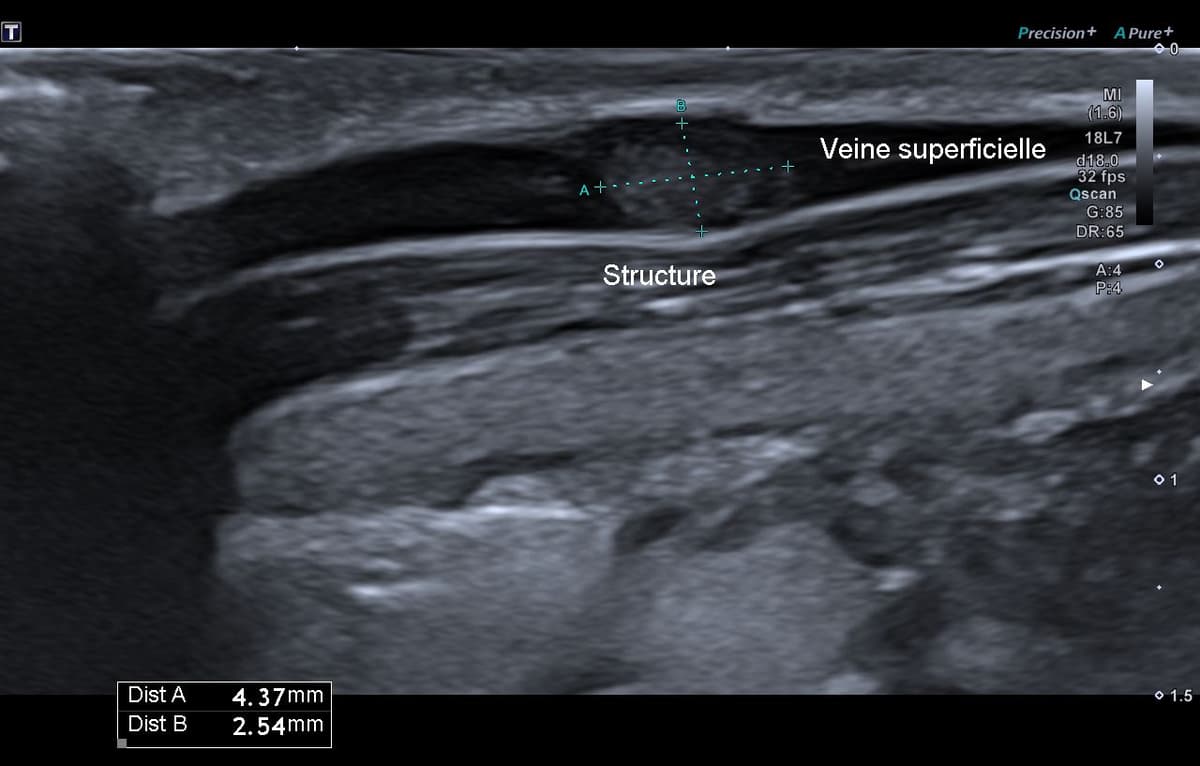

Tumeur de Masson

Tuméfaction indolore latéro-cervicale d'apparition spontanée à évolution lente.

US